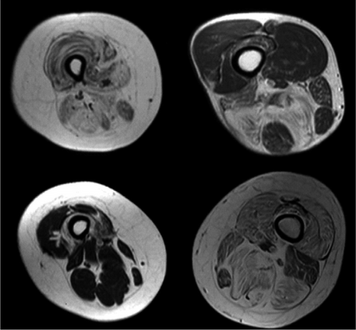

Diagnostic procedures that may reveal muscular disorders include direct clinical observations. This usually starts with the observation of bulk, possible atrophy or loss of muscle tone. Neuromuscular disease can also be diagnosed by imaging, various blood tests and using electrodiagnostic medicine tests[19] including electromyography[20] (measuring electrical activity in muscles) and nerve conduction studies.[21] Genetic testing is an important part of diagnosing inherited neuromuscular conditions.[19]

Radiologic imaging in neuromuscular disorders